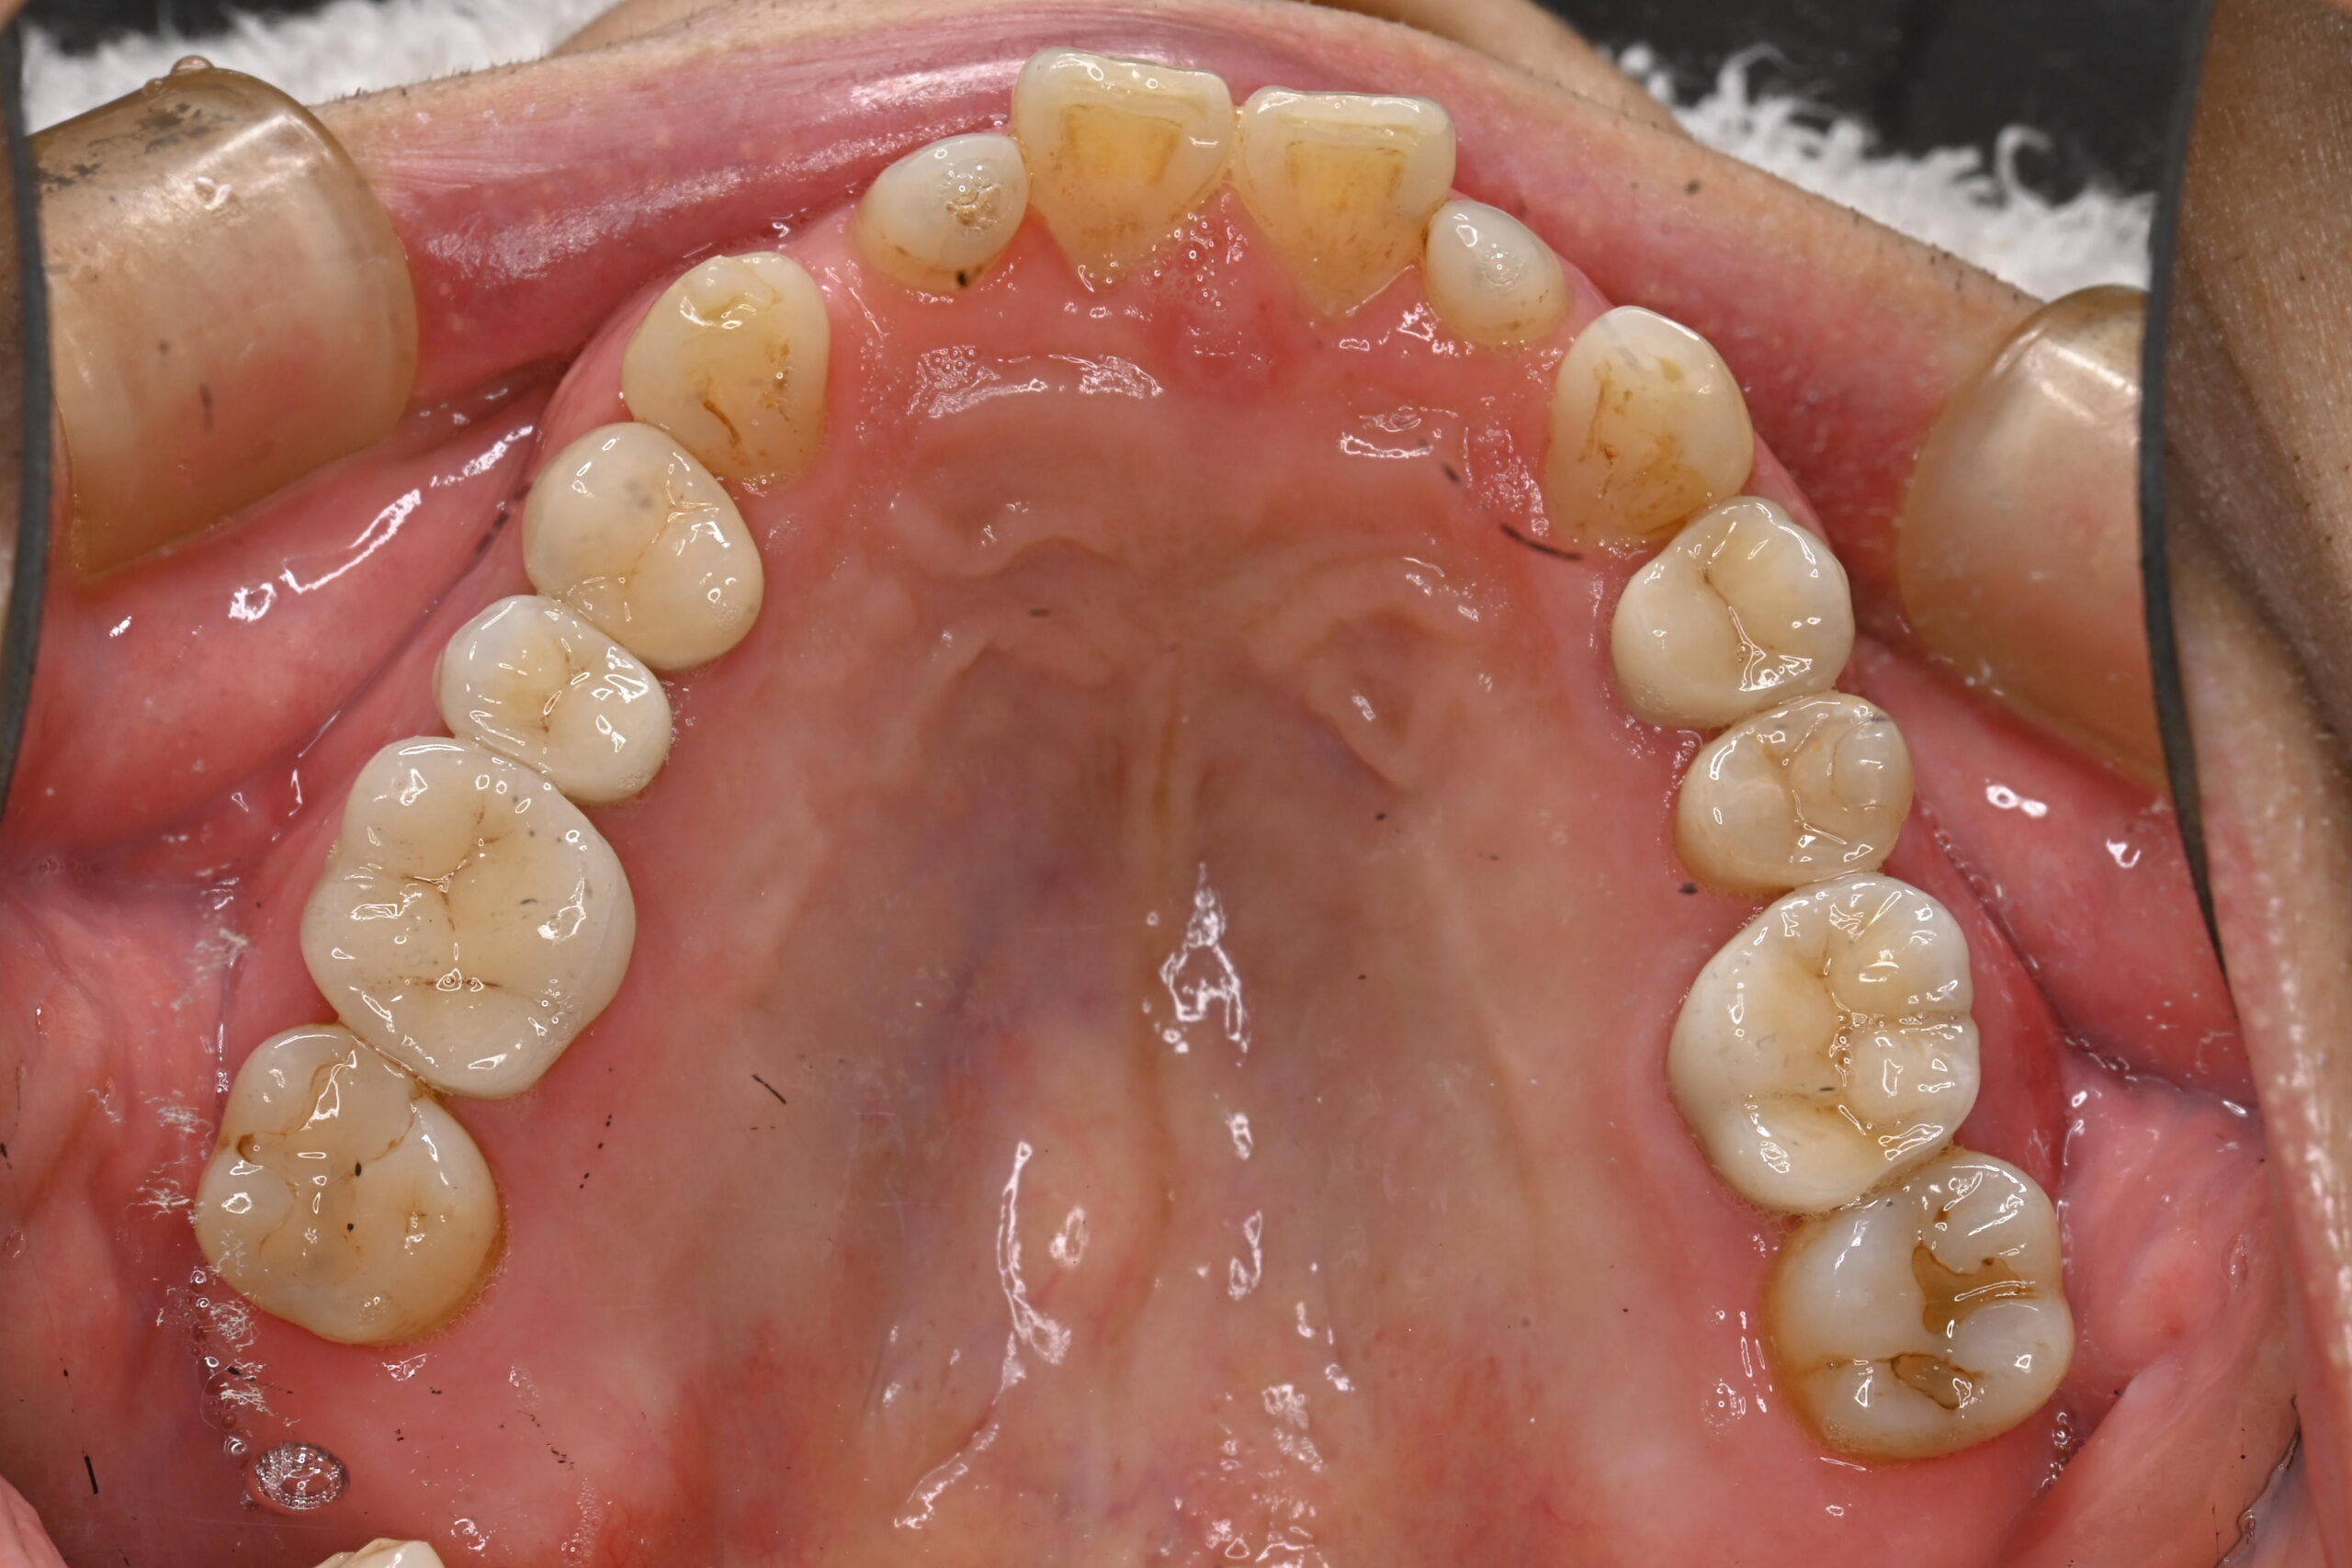

症例写真 before